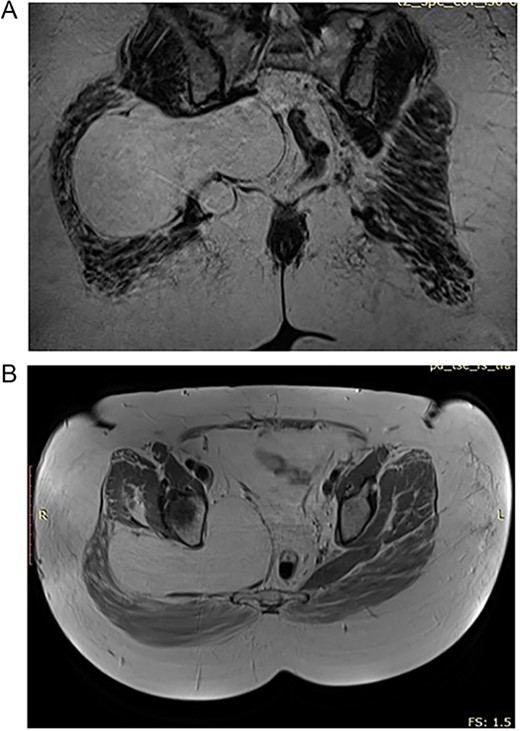

A curvilinear incision is made in the direction of the gluteal fibers, centered on the intertrochanteric crest, and extended inferiorly along the femoral shaft. The incision originates 5 cm below and just lateral to the posterior inferior iliac spine, in alignment with the inferior border of the piriformis muscle (Fig. 3A).

(A) Transgluteal approach used for excision of the lipomatosus lesion. (B) Complete resection of the lesions and intraoperative measurement of its sizes.

Following the initial incision, the gluteal fascia and iliotibial tract are meticulously incised in alignment with the overlying skin incision. Subsequently, the fibers of the gluteus maximus are methodically separated, commencing laterally and advancing medially. Blunt dissection and careful tissue separation enabled effective hemostasis, ensuring a clean and dry surgical field [8].

This technique facilitated the en bloc removal of the capsule along an extracapsular plane, a critical step in achieving the complete resection of the lesion (Fig. 3B).